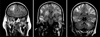

Fig. 3

Coronal T2 weighted brain imaging (radiologic view: right is left and left is right) at 3.5-year follow-up. The scan on the left shows a view through the frontal lobes showing marked brain atrophy with sulcal widening. The middle scan shows a view through the hippocampus, showing enlargement of the temporal horns of the lateral ventricles, mild hippocampal atrophy, and sulcal widening. The right scan shows a view through the posterior temporal and parietal lobes and cerebellum with marked brain atrophy with sulcal widening and ventricular enlargement.